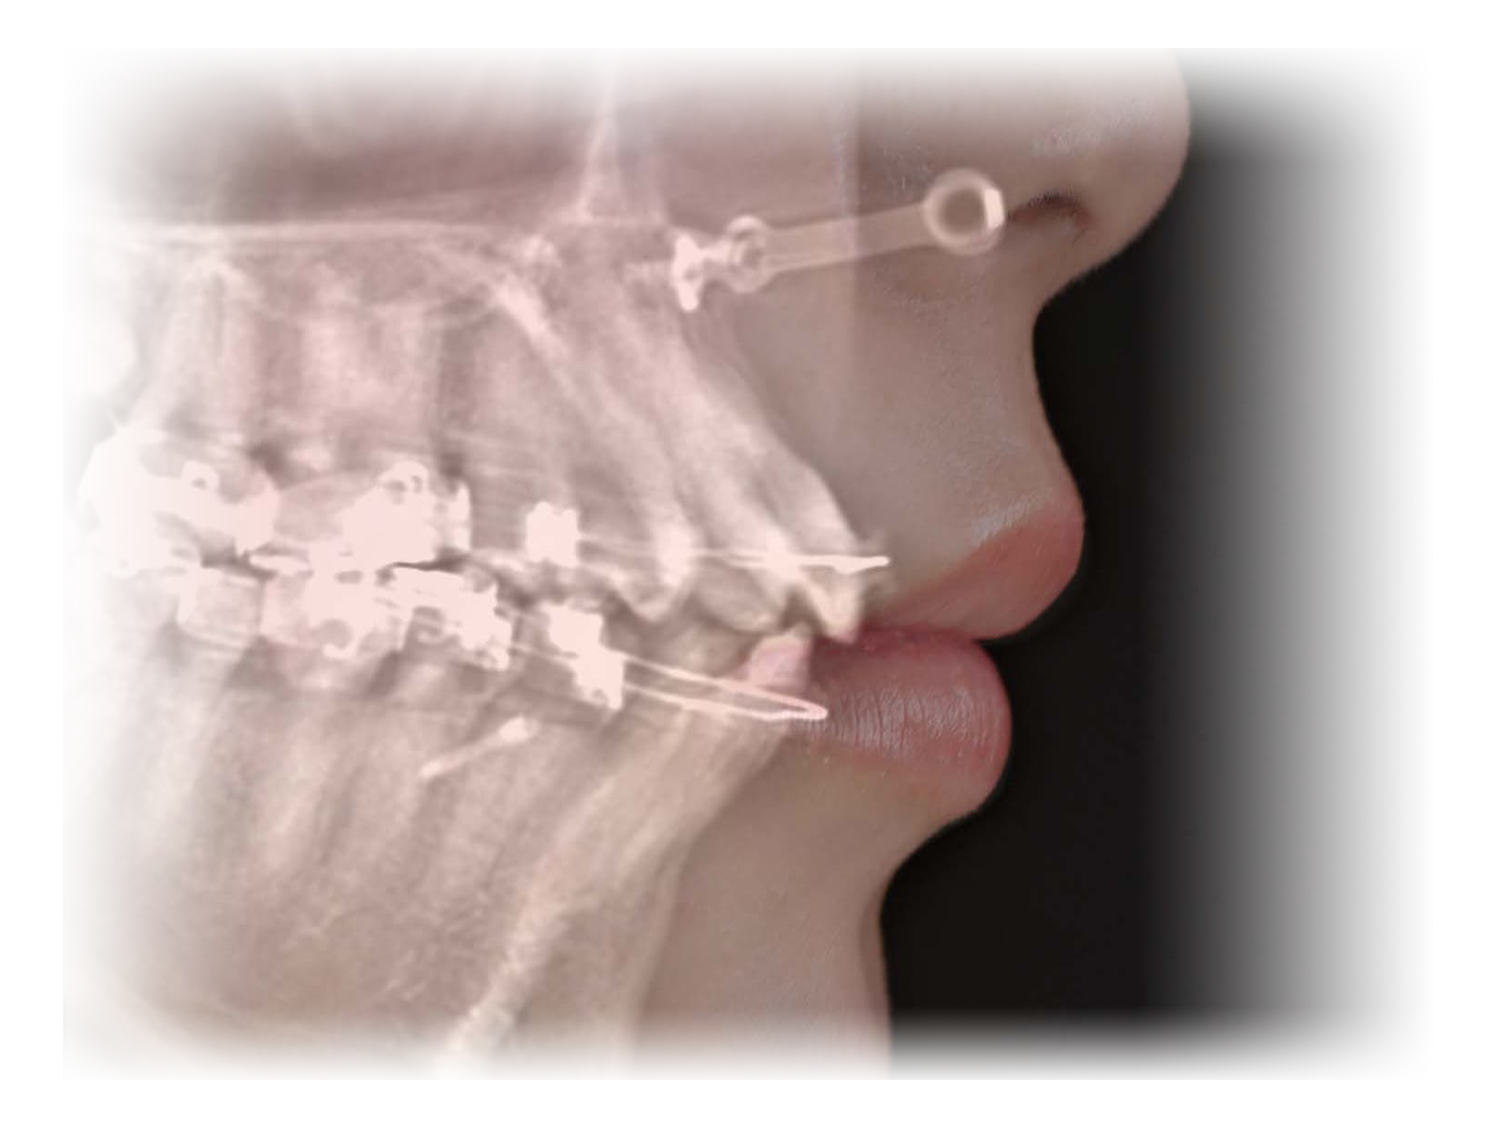

A点手術

チタンプレートを用いて

鼻の下を前方に出すことで、

1)顔の立体感

2)加齢により後ろに下がる鼻下部分の改善

を目的とした治療になります。

A点+α手術

A点手術に改良を加えて人工真皮とプレートを鼻翼基部に移植することで、より顔貌の立体感を得ることができる治療になります。